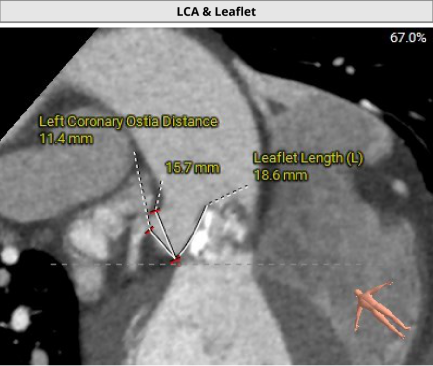

2. 冠脉开口高度尚可,左右冠瓣叶冗长,切线位左右冠瓣叶长度>>冠脉开口到瓣叶根部附着缘距离;冠脉未见明显钙化斑块;

冠脉阻挡风险及钙化评估

• 左右冠瓣叶冗长,切线位左右冠瓣叶长度>>冠脉开口到瓣叶根部附着缘距离,结合瓦氏窦、STJ、钙化分布特点综合预估冠脉堵塞风险偏高,术中球扩时密切关注冠脉血流灌注,备冠脉保护方案;